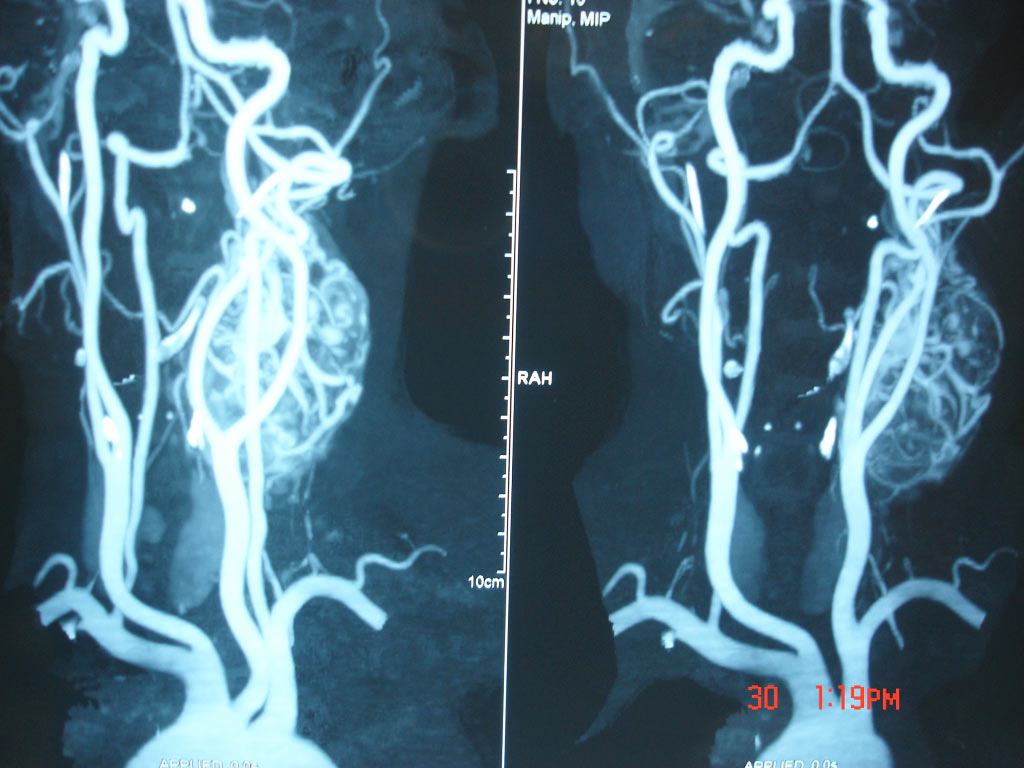

Uterine Artery Embolization